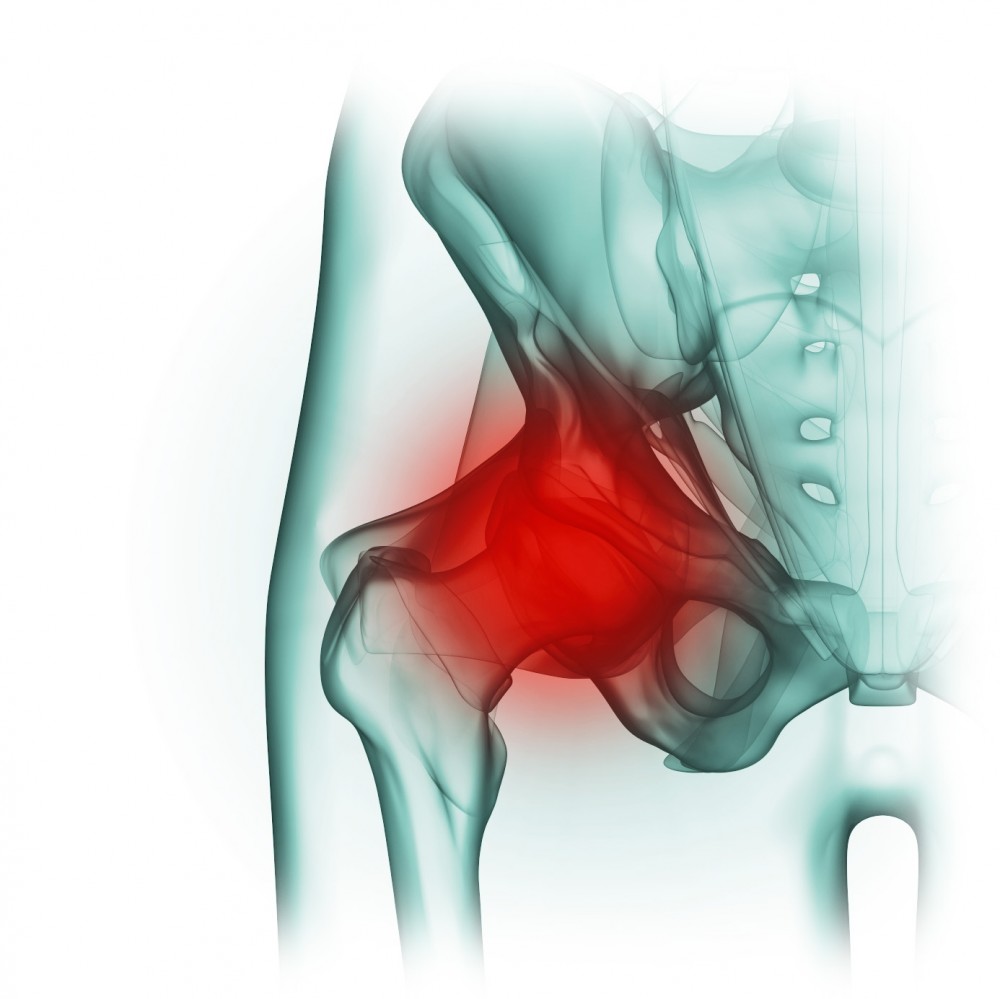

Здоровье суставов: Трохантерит и его влияние на мышцы